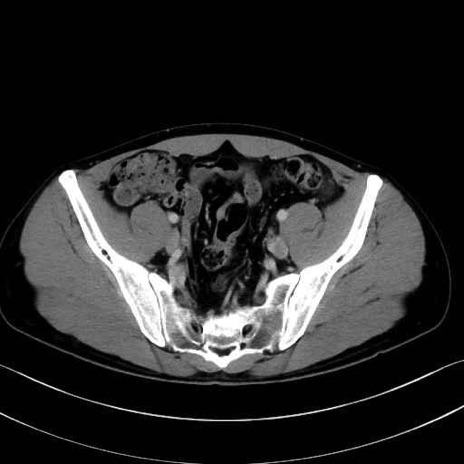

2. 腸腰筋群と骨盤底筋

大腰筋 (Psoas major)

腸骨筋 (Iliacus)

肛門挙筋 (Levator ani)

3. 殿部の筋肉(表層・中層・深層)

大殿筋 (Gluteus maximus)